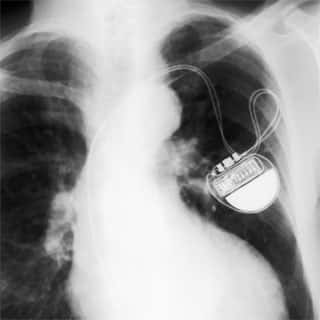

Marcapasso cardiológicoDevemos o desenvolvimento desse equipamento, muito utilizado nos dias de hoje, aos trabalhos de um famoso cardiologista, Paulo Maurice Zoll, que durante grande parte de sua carreira, dedicou-se ao estudo dos estímulos elétricos no coração, com a finalidade de evitar paradas cardíacas.

Zoll estimulava eletricamente o coração através de eletrodos externos, colocados no peito do paciente. Hyman concluiu que se os estímulos fossem feitos diretamente no coração, os resultados seriam melhores.

Somente após a II Guerra Mundial, por volta de 1950, foi desenvolvido um marcapasso totalmente eletrônico, mas volumoso. Somente após o desenvolvimento dos transistores é que os marcapassos foram realmente miniaturizados, chegando a volumes compatíveis com sua inserção no coração.